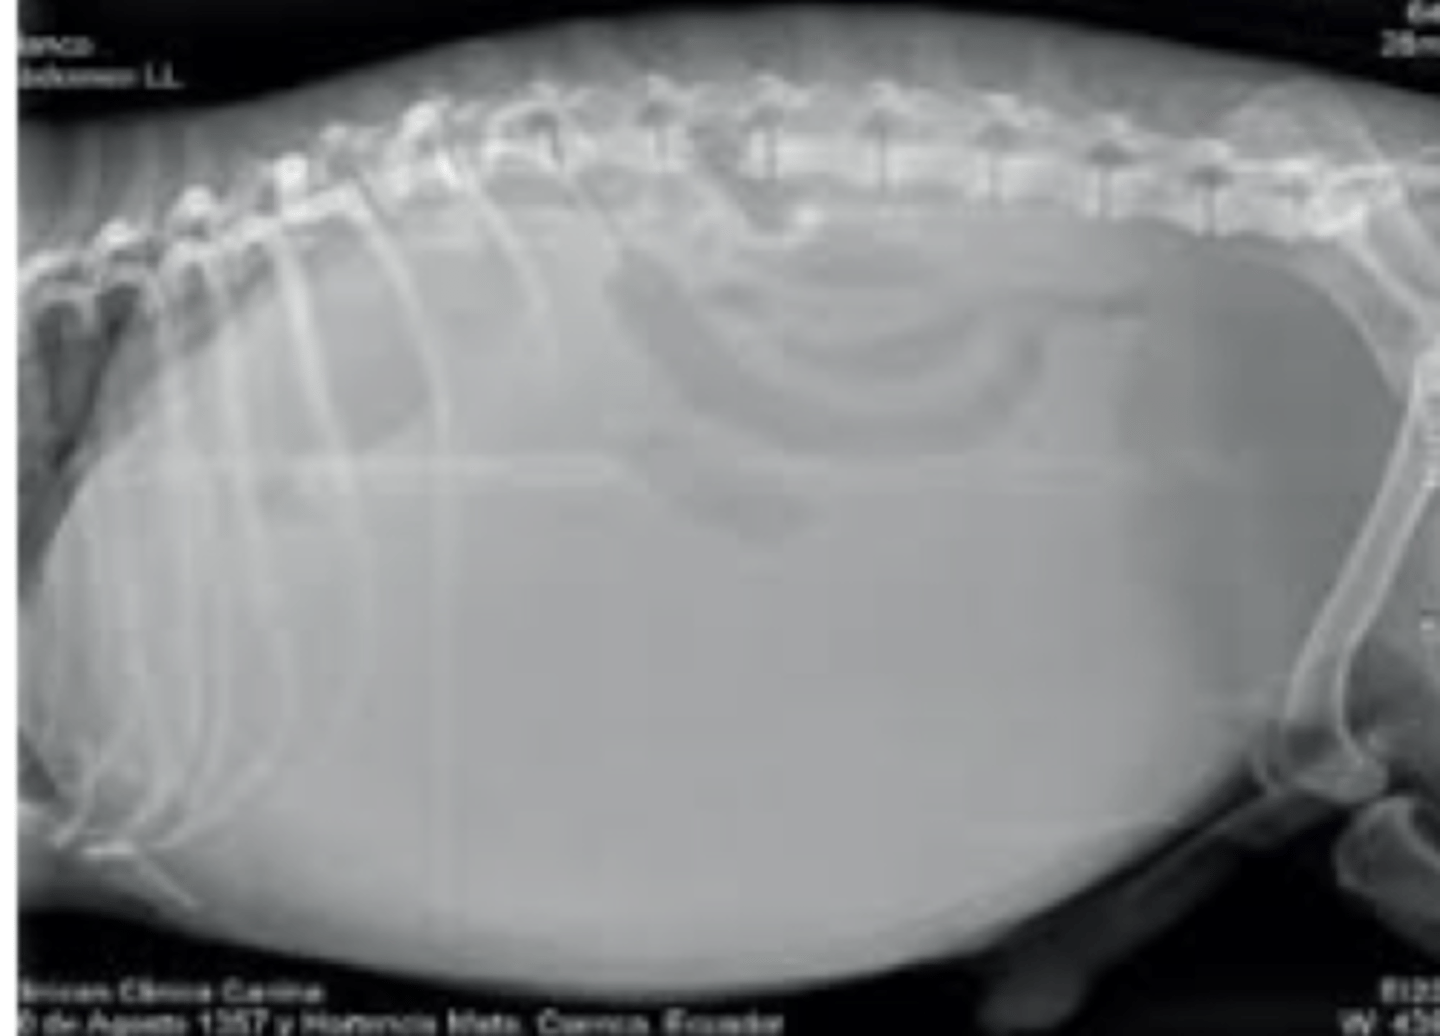

efusión abdominal

patología: